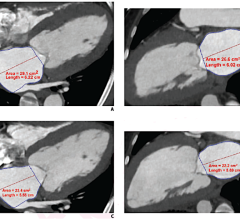

Currently, subtracting bone from neurological CT angiography procedures requires that physicians scan the brain twice, once with contrast and once without contrast, and then manually subtract bone structures from the image to better visualize the vessels and tissue. Toshiba’s SURESubtraction technology automates the bone subtraction process, reducing exam time by a reported 90 percent, according to the manufacturer.

SURESubtraction is an option for Toshiba’s 8-, 16-, 32- and 64-slice CT systems. Given the software’s ability to detect and subtract bone from images, it offers a number of clinical applications, including:

- Cerebral aneurysms – especially close to the bone

- Patients with ischemic disease – ICA, basilar artery

- Cases with stenosis or occlusion – close to bone